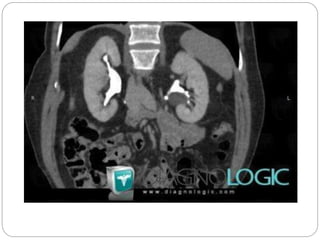

Parapelvic cyst

Severe hydronephrosis with

proximal hydro ureter

Moderate hydronephrosis on

right and severe on left